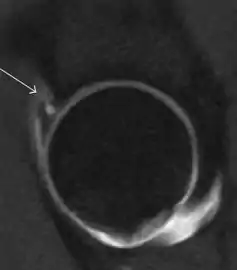

Most of the angles and measurements described in the plain radiograph section can be accurately reproduced on MRI. In addition, the superiority of MRI resolution with intra-articular contrast allows detection of labral and chondral abnormalities that may influence the choice of medical, percutaneous, or surgical management (Figure 9).[1]

Figure 9:

MR arthrography has proven superior in accuracy when compared to native MR imaging. It is considered the best technique to assess the labrum. Knowledge of the normal variable morphology of the labrum helps to differentiate tears from normal variants. A triangular shape is most commonly seen in 66% of asymptomatic volunteers, but round, flattened, and absent labra can also be found in asymptomatic populations. MR arthrography has demonstrated sensitivity over 90% and specificity close to 100% in detecting labral tears. Loose bodies are demonstrated as filling defects surrounded by the hyperintense gadolinium.[1]

Association between labral tears and chondral damage has been demonstrated. This underscores the interaction between cartilage and labrum damage in the progression of osteoarthritis. Chondral damage to the posteroinferior part of the acetabulum as a contrecoup lesion occurs in approximately one-third of pincer cases secondary to persistent abutment on the anterior part of the joint leading to a slight posteroinferior subluxation. This is considered a bad prognosis sign.[1]

MR arthrography can also demonstrate ligamentum teres rupture or capsular laxity, which are debated causes of microinstability of the hip. Elongation of the capsule or injury to the iliofemoral ligament or labrum may be secondary to microtrauma in athletes. MR can demonstrate abnormalities in these cases, such as increased joint volume or a ligamentum teres tear (Figure 9).[1]